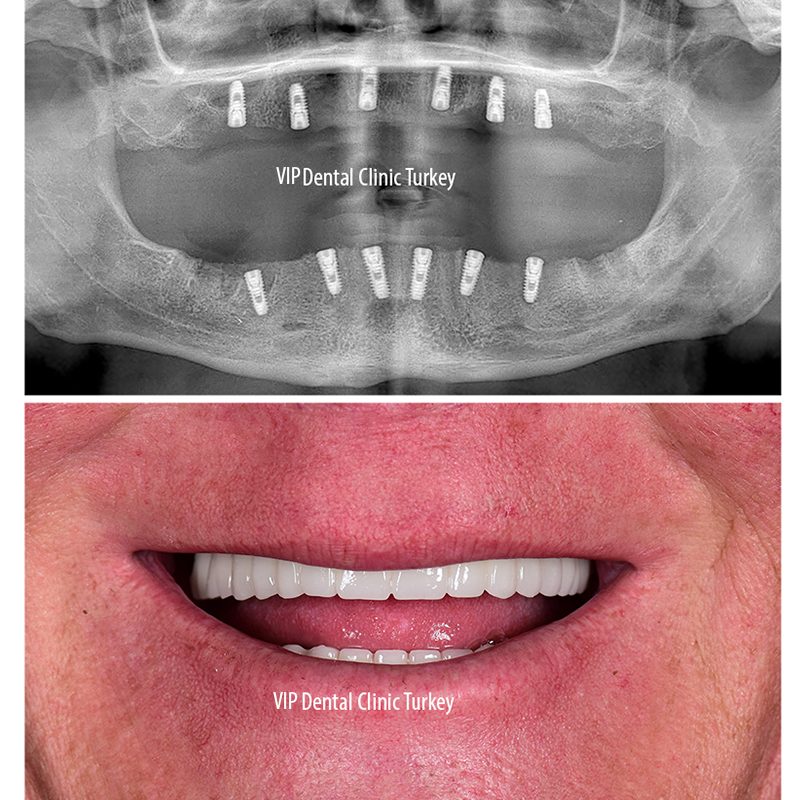

Alors que les personnes qui viennent se faire des dents en Turquie préfèrent généralement les traitements esthétiques dentaires tels que le placage, le blanchiment des dents, l’esthétique rose, les traitements implantaires sont l’une des raisons les plus populaires de la migration sanitaire. Les patients qui reçoivent la plupart de ces traitements parce qu’ils les considèrent plus abordables que les alternatives dans leur propre pays, s’adressent intensivement à notre pays pour les maladies dentaires.

Avant le traitement, la personne doit consulter un médecin sur la procédure qu’elle souhaite subir et si cette procédure lui convient. Si le médecin approuve et confirme le traitement à effectuer, il doit d’abord partager les informations sur le traitement, telles que les résultats de la radiographie et des tests avec les médecins de la clinique où le traitement aura lieu dans notre pays. Ainsi, le médecin peut ici fournir des informations plus détaillées sur la procédure à effectuer, ainsi qu’informer plus clairement le coût du traitement. Ainsi, le patient aura une perspective plus claire sur l’opportunité de recevoir ou non un traitement.